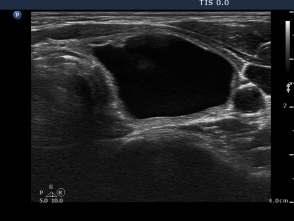

Second session of sclerotherapy (third row of images):

The second session was performed nine days after the previous one. The nodule became a bit larger. Now we could aspirated 15 mL brown fluid form the nodule, therafter we injected 5 mL ethanol.